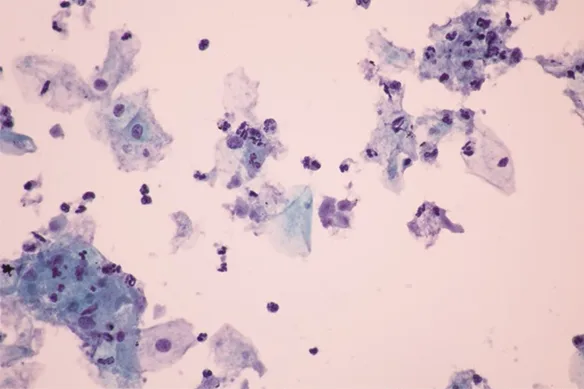

Πολλές μελέτες συσχετίζουν μια συχνά σεξουαλικά μεταδιδόμενη λοίμωξη, τις τριχομονάδες, με τον καρκίνο του προστάτη. Οι ερευνητές πλέον υποστηρίζουν ότι οι πιθανότητες εμφάνισης του συγκεκριμένου καρκίνου αυξάνονται στους άνδρες που έχουν μολυνθεί.

Το παρασίτου Trichomonas vaginalis που προκαλεί την τριχομονίαση (τριχομονάδες), εκκρίνει μια πρωτεΐνη που διεγείρει την ανάπτυξη των κυττάρων του προστάτη και επίσης προκαλεί μια φλεγμονώδη αντίδραση, η οποία οι ερευνητές υποψιάζονται ότι ενισχύει την εξαλλαγή των κυττάρων σε καρκινικά κύτταρα, καθώς και ότι βοηθάει τα κύτταρα του καρκίνου του προστάτη να μεγαλώσουν και να αναπτυχθούν ταχύτερα. Επίσης διαπιστώθηκε ότι οι άνδρες με αντισώματα έναντι του T. vaginalis είχαν διπλάσιες πιθανότητες να αναπτύξουν μια επιθετική μορφή καρκίνου του προστάτη που κάνει μεταστάσεις.

«Προκαλούμενη από το ένα μικροσκοπικό, μονοκύτταρο πρωτόζωο-παράσιτο, το Trichomonas vaginalis, η τριχομονίαση (τριχομονάδες), είναι μία από τα συχνότερα σεξουαλικά μεταδιδόμενα νοσήματα.